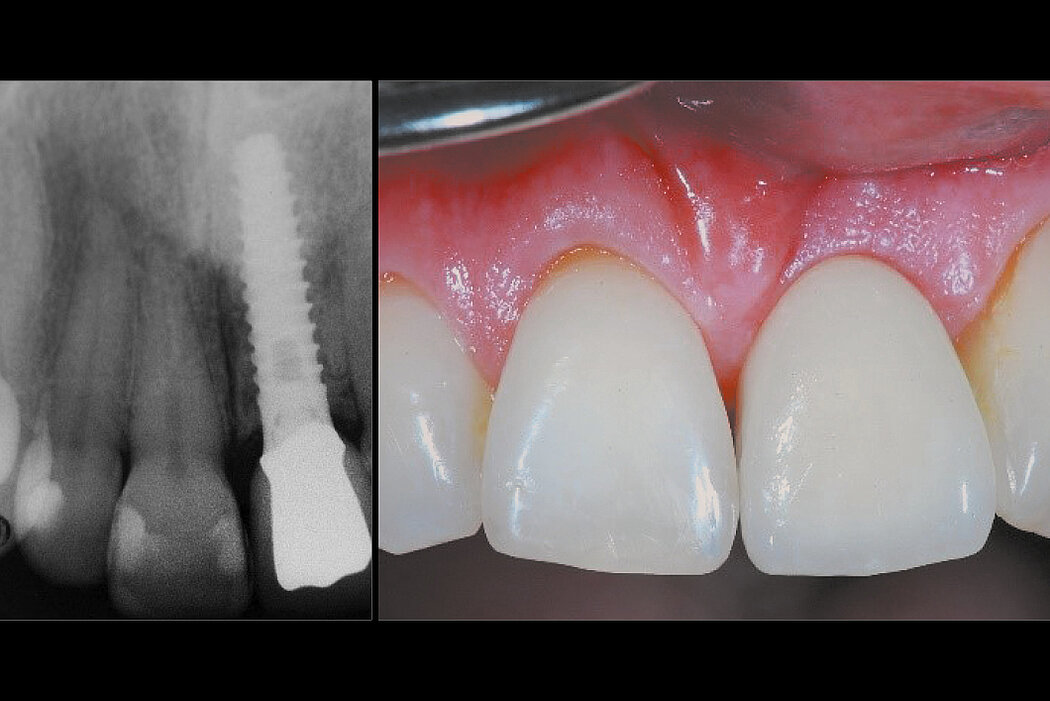

Delayed implant placement 4 months after extraction. Minimally invasive treatment of the socket.

Good/mature/solid bone obtained 4 months after treatment. Fast and scar-free soft tissue regeneration. Optimal clinical and esthetic result for the patient.